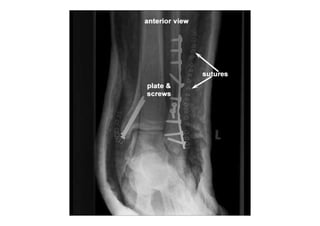

RADIOLOGIA DO

TRAUMA DO ESQUELETO

Referência: http://www.accessexcellence.org/RC/VL/